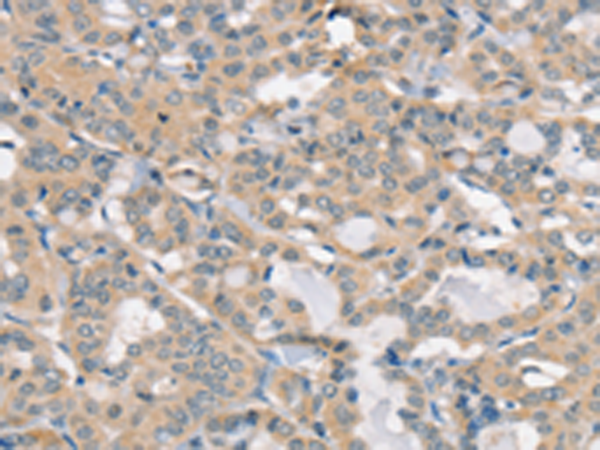

分类: 科研抗体货号: P12174别名: SIR2L4应用: IHC反应种属: Human, Mouse